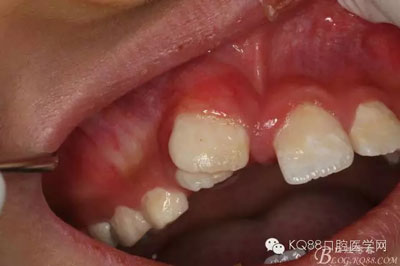

患者、孫xx、男、10歲。主訴:上前牙排列不齊,要求治療。??茩z查:11與21之間有間隙約3mm,11唇側(cè)傾斜,12位于11是腭側(cè)萌出,11與12完全唇腭向重疊。cbct檢查:11與21之間有一倒置多生牙,多生牙牙根位于11與21之間,牙冠位于11與12之間。診斷:埋伏倒置多生牙。治療建議:1.建議拔除倒置多生牙。2.多生牙拔除后,建議早期正畸治療?;颊咄馐中g(shù)方案,簽知情同意書(shū)。

圖1.術(shù)前的患者口內(nèi)照片:11與12完全唇腭向重疊,11與21之間有3mm間隙